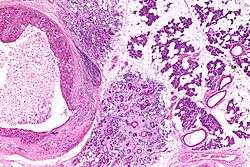

| Low magnification micrograph of a salivary duct carcinoma with characteristic comedonecrosis (left of image) adjacent to normal parotid gland (right of image). H&E stain. | |

Their histologic appearance is similar to ductal breast carcinoma.

Very low mag.

Intermed. mag.